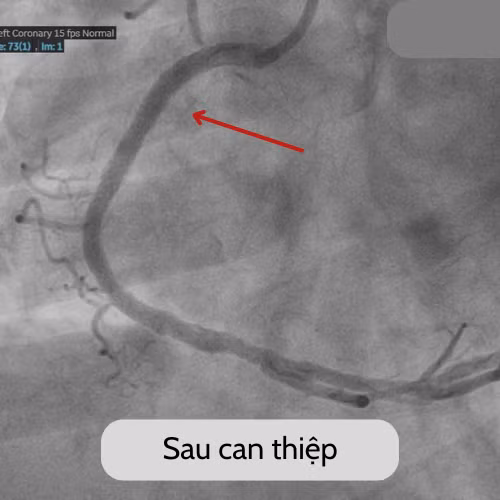

| Hình ảnh trước và sau can thiệp của bệnh nhân u - Ảnh BVCC |

Trong lúc đó, quy trình báo động đỏ toàn viện cũng được kích hoạt, các bộ phận trong quy trình can thiệp cấp cứu chuẩn bị sẵn sàng. Ngay khi đón người bệnh, các bác sĩ đã chỉ định chụp mạch vành, kết quả cho thấy người bệnh tắc hoàn toàn đoạn gần của động mạch vành phải, chỉ định can thiệp nong và đặt stent tại vị trí tắc mạch.

Ekip bác sĩ khoa Nội tim mạch BVĐK Xuyên Á đã tiến hành can thiệp nong và đặt stent, ngay sau can thiệp, dòng máu đã được tái thông tốt. Như vậy, nhờ can thiệp cấp cứu kịp thời thời mà người bệnh đã thoát khỏi giai đoạn nguy hiểm, hồi phục rất tốt và đã được xuất viện chỉ vài ngày sau đó.